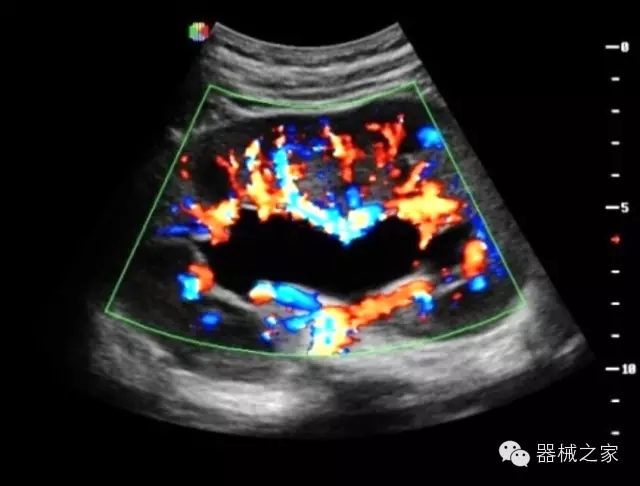

品牌:開立(SONOSCAPE)

公司簡介:

深圳開立生物醫(yī)療科技股份有限公司作為中國民族醫(yī)療產(chǎn)業(yè)的優(yōu)秀引導(dǎo)者,自成立伊始,一直致力于臨床醫(yī)療設(shè)備的研發(fā)和制造,產(chǎn)品涵蓋醫(yī)用數(shù)字超聲診斷系統(tǒng)、電子內(nèi)窺鏡系統(tǒng)、全自動(dòng)五分類血液細(xì)胞分析儀以及自主研發(fā)的探頭群。

官方網(wǎng)站:www.sonoscape.com.cn

經(jīng)典產(chǎn)品:S8EXP

臨床圖片賞析

產(chǎn)品特點(diǎn)

優(yōu)異的成像技術(shù)

·亞陣元技術(shù):獨(dú)有的亞陣元技術(shù),對獨(dú)立晶片做二次切割,減少旁瓣偽像,增加臨床診斷的準(zhǔn)確性;

·μ-Scan微米成像技術(shù):開立獨(dú)有的μ-Scan技術(shù),還原出真實(shí)細(xì)膩、層次對比優(yōu)異的二維圖像;

·倒相諧波成像技術(shù):倒相諧波技術(shù)在去除基波信號的基礎(chǔ)上獲取兩倍二次諧波信號,提高組織圖像的對比分辨力;

·智能微血流成像技術(shù):智能微血流捕捉技術(shù)可以提取出隱藏在背景噪聲中的弱血流信號,大大提高低速血流的敏感性;